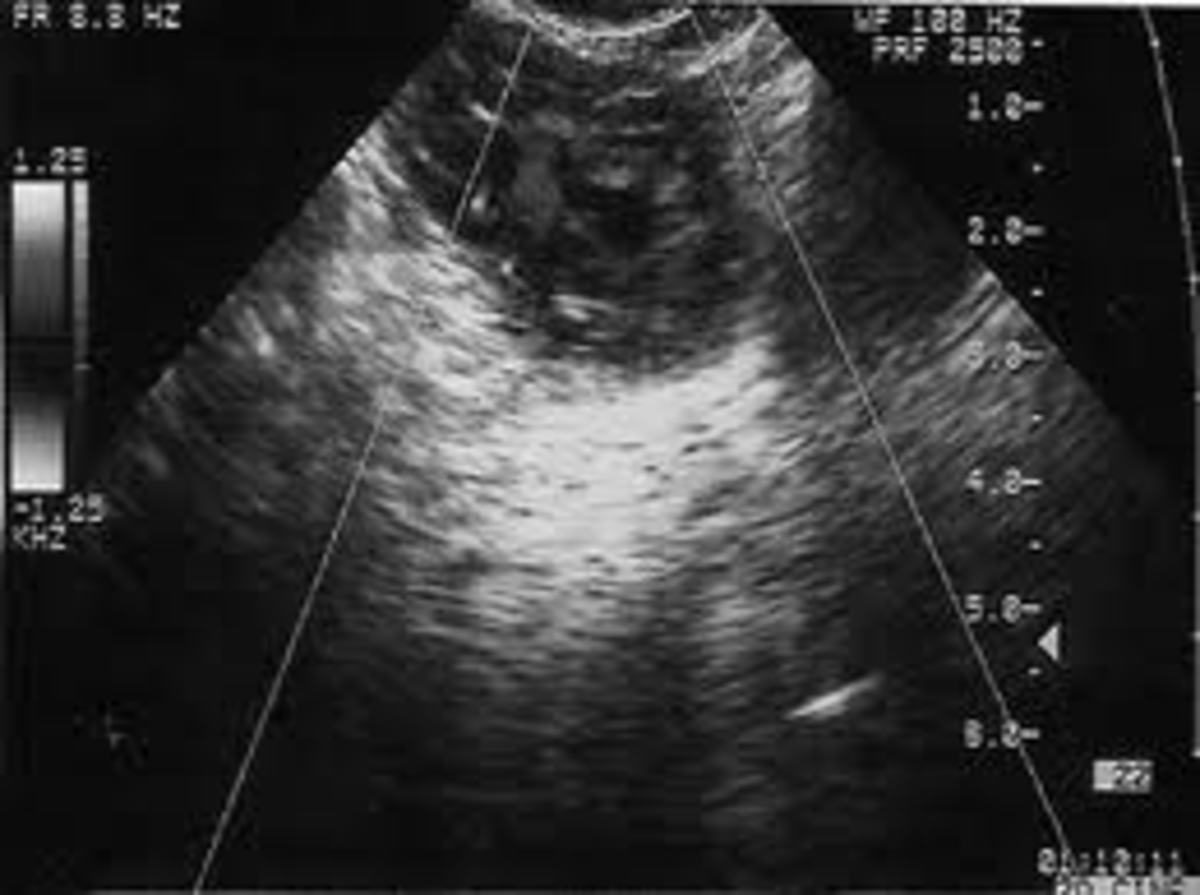

Σήμερα έχουμε τόσο εργαστηριακές εξετάσεις, όσο και το διακολπικό υπερηχογράφημα, που μπορούν να επισπεύσουν τη διάγνωση. Όμως ακόμα και με τα μέσα αυτά πολλές φορές η διάγνωση είναι δύσκολη.

Πολύ χρήσιμος στα πλαίσια της διάγνωσης εξωμήτριου κύησης είναι και ο υπερηχογραφικός έλεγχος. Αν γίνει διακολπικό υπερηχογράφημα, όταν τα επίπεδα της β-hcg στο αίμα είναι από 1000 μέχρι 2000 mIU/ml και δεν εντοπισθεί κύημα εντός της μήτρας, τότε αυξάνονται σημαντικά οι πιθανότητες για εξωμήτριο κύηση.

Αυτά τα επίπεδα β-hcg υφίστανται σε πολύ αρχικά στάδια της κύησης. Τότε το κύημα είναι πολύ μικρό και είναι σχεδόν αδύντατο να το εντοπίσουμε ετκός της μήτρας, ενώ εντός της μήτρας, όπου και ο χώρος εξέτασης είναι περιορισμένος, εντοπίζεται σχετικά εύκολα. Έτσι η υποψία εξωμήτριου κύησης προκύπτει έμμεσα: αφού δεν βλέπουμε κύημα μέσα στη μήτρα και η κύηση υπάρχει, όπως φαίνεται από τα επίπεδα της β-hcg, τότε μάλλον η κύηση είναι εξωμήτριος.

Με τον υπερηχογραφικό έλεγχο είναι όμως δυνατόν να εντοπίσουμε το κύημα εκτός μήτρας, αν η κύηση έχει προχωρήσει και αυτό είναι αρκετά μεγάλο. Έτσι στην περίπτωση αυτή δεν μιλάμε πια για υποψία αλλά για βεβαιότητα ύπαρξης εξωμήτριου κύησης.